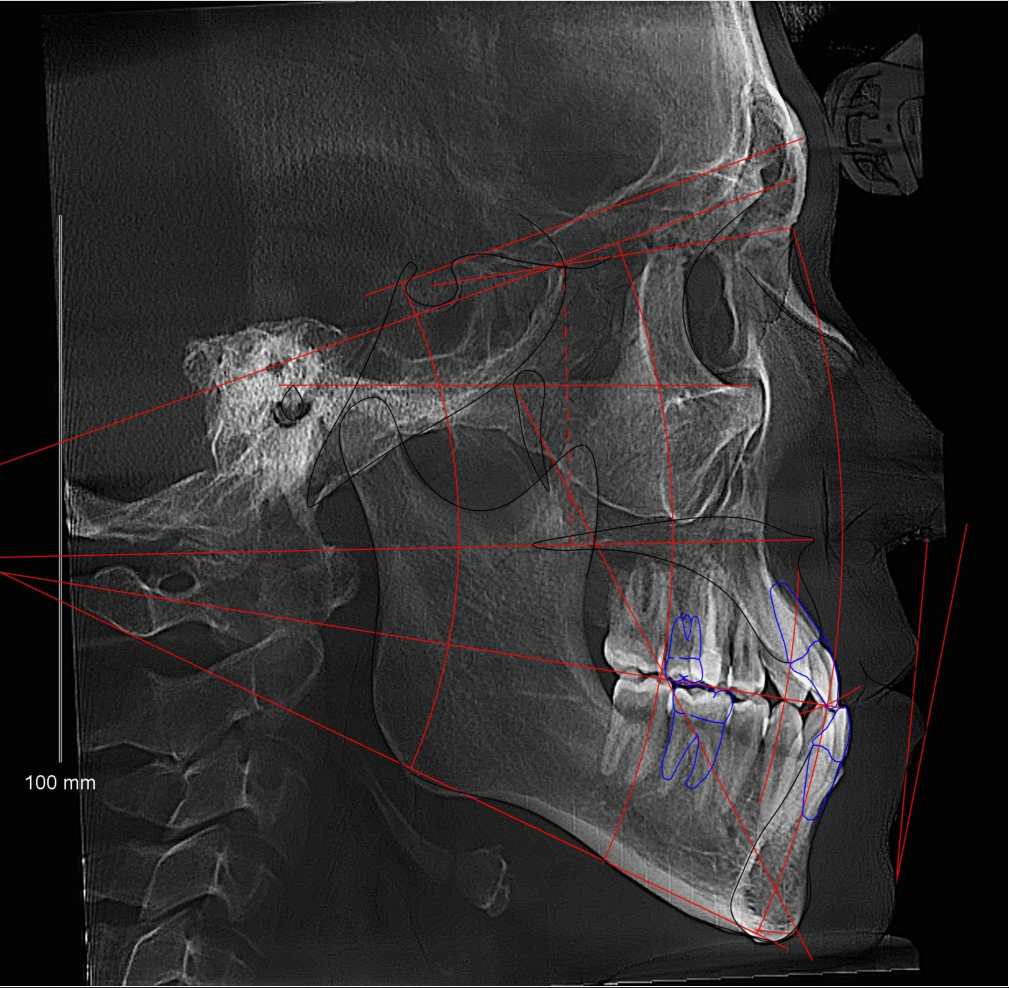

призвыаю всех пиливших челюсти по квоте в тред похоже, мой путь только начинается, чё раскажете инте